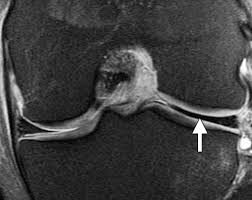

Meniscal tear can be well appreciated on an mri. In humans they are present in the knee, wrist, acromioclavicular, sternoclavicular, and temporomandibular joints; In other animals they may be present in other joints.

During knee flexion, the menisci are pulled dorsally by the femoral condyles.

Circle of villis angiogram anatomy mri. The posterior horn is always larger than the anterior horn. Meniscus rupture can occur with a sharp movement in the lateral direction, or in a direction that goes beyond the. Magnetic resonance (mr) imaging of the knee and ankle is playing an increasingly important role in the detection, diagnosis and prognosis of these injuries and their associated complications.